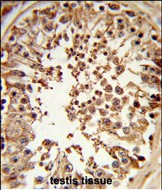

IHC 1/100-1/500 Human,Mouse,Rat

The DMC1 (N-term) antibody is a tool used to study the DNA meiotic recombinase 1 (DMC1) protein, a key enzyme in homologous recombination during meiosis. DMC1 is evolutionarily conserved and plays a critical role in repairing double-strand DNA breaks (DSBs) by facilitating strand exchange between homologous chromosomes, ensuring accurate chromosome segregation and genetic diversity. The protein is predominantly expressed in germline cells, where meiosis occurs, and its dysfunction has been linked to infertility and reproductive disorders. The N-terminal region of DMC1 is essential for its oligomerization and interaction with other recombination proteins, such as RAD51. to form functional nucleoprotein filaments.

The DMC1 (N-term) antibody specifically targets the N-terminal domain of the protein, enabling researchers to detect and analyze DMC1 expression, localization, and dynamics in meiotic cells. It is widely used in techniques like Western blotting, immunofluorescence, and immunohistochemistry in model organisms (e.g., mice, plants) and human tissues. Studies employing this antibody have advanced our understanding of meiotic mechanisms, crossover formation, and genome stability. Validation of the antibody typically includes testing in DMC1-knockout models or siRNA-treated cells to confirm specificity. Its applications extend to reproductive biology research, cancer studies (due to overlaps in DNA repair pathways), and diagnostics for gametogenesis-related disorders.